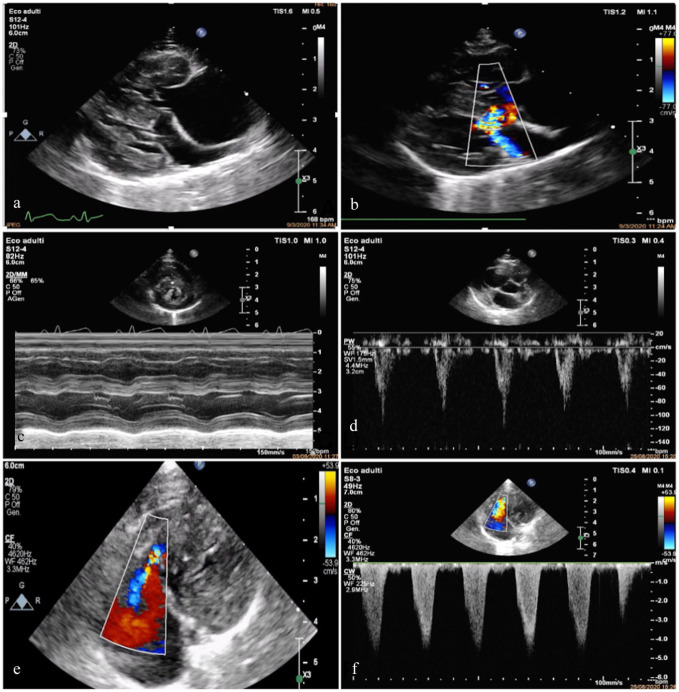

病例摘要:本报告描述了一只患有肺发育疾病和肺动脉高压高风险的幼猫的候选基因叉头盒 F1 (FOXF1) 的诊断结果、自然病史和遗传分析。一只 1 岁大的雄性全Chartreux猫因心脏杂音调查和运动不耐受而被转诊。超声心动图检查发现三尖瓣反流射流速度较快,并伴有右侧心脏变化,肺动脉高压的可能性很高。没有发现先天性心脏分流或左侧心脏病变,支持肺动脉高压的原发性心脏病因。对患者进行了广泛的实验室检查、胸部X光检查和CT检查。组织病理学鉴定(肺活检和随后的尸检)是最终诊断的必要条件。确诊八个月后,该猫出现右侧充血性心力衰竭,最终导致安乐死。从确诊到死亡的存活期为 12 个月:发育性肺病属于人类弥漫性肺病的一种,与肺动脉高压有关。描述猫肺发育障碍的兽医文献很少,本报告提供了有关临床表现和病情发展的信息以及全面的诊断工作,这可能有助于临床医生识别这种疾病。肺部活检是最终诊断的关键。未发现 FOXF1 的致病变异。

Case summary: This report describes the diagnostic findings, natural history and genetic analysis of the candidate gene Forkhead Box F1 (FOXF1) in a young cat with developmental lung disease and high probability of pulmonary hypertension. A 1-year-old male entire Chartreux cat was referred for cardiac murmur investigation and exercise intolerance. Echocardiography identified a high-velocity tricuspid regurgitant jet with right-sided cardiac changes, supporting a high probability of pulmonary hypertension. No congenital cardiac shunts or left-sided cardiac changes were found to support a primary cardiac cause of pulmonary hypertension. Extensive laboratory work, thoracic radiographs and CT were performed. Histopathological characterisation (lung biopsy and later post mortem) was necessary to reach the final diagnosis. Eight months after diagnosis, the cat developed right-sided congestive heart failure, eventually leading to euthanasia. Survival from diagnosis to death was 12 months.